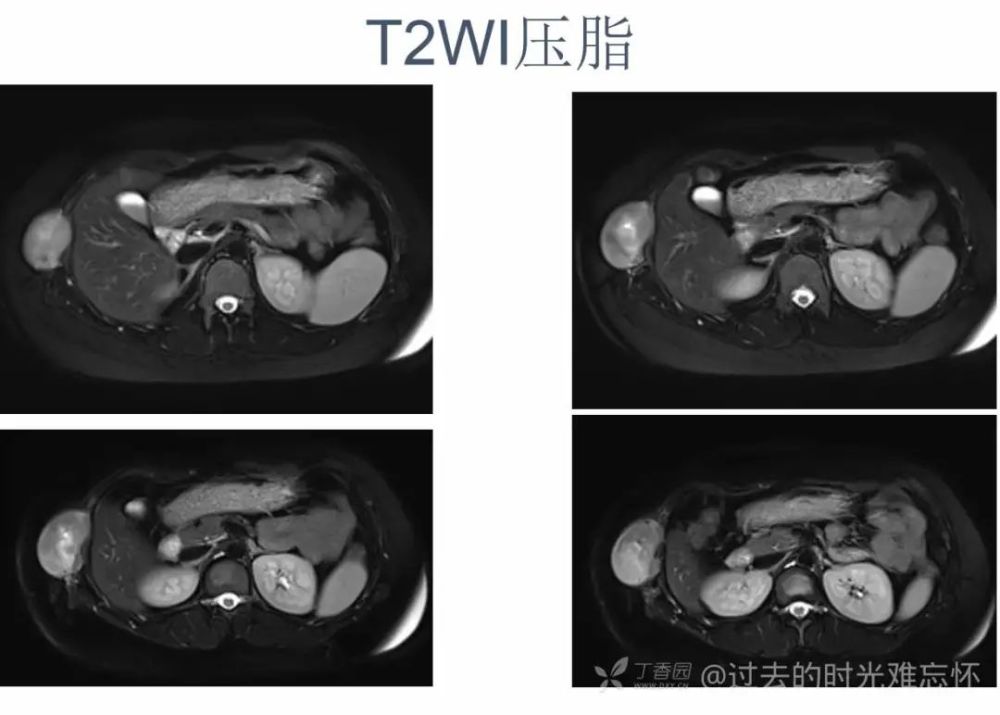

女,22 岁。右下侧胸壁疼痛、不适 10 年,近 3 年发现右侧腋中线近肋弓处肿块。体检:局部皮肤无红肿,肿块质中等偏硬,活动度欠佳,压痛( + ),无血管杂音。超声描述「低回声包块」。化验室指标无异常。